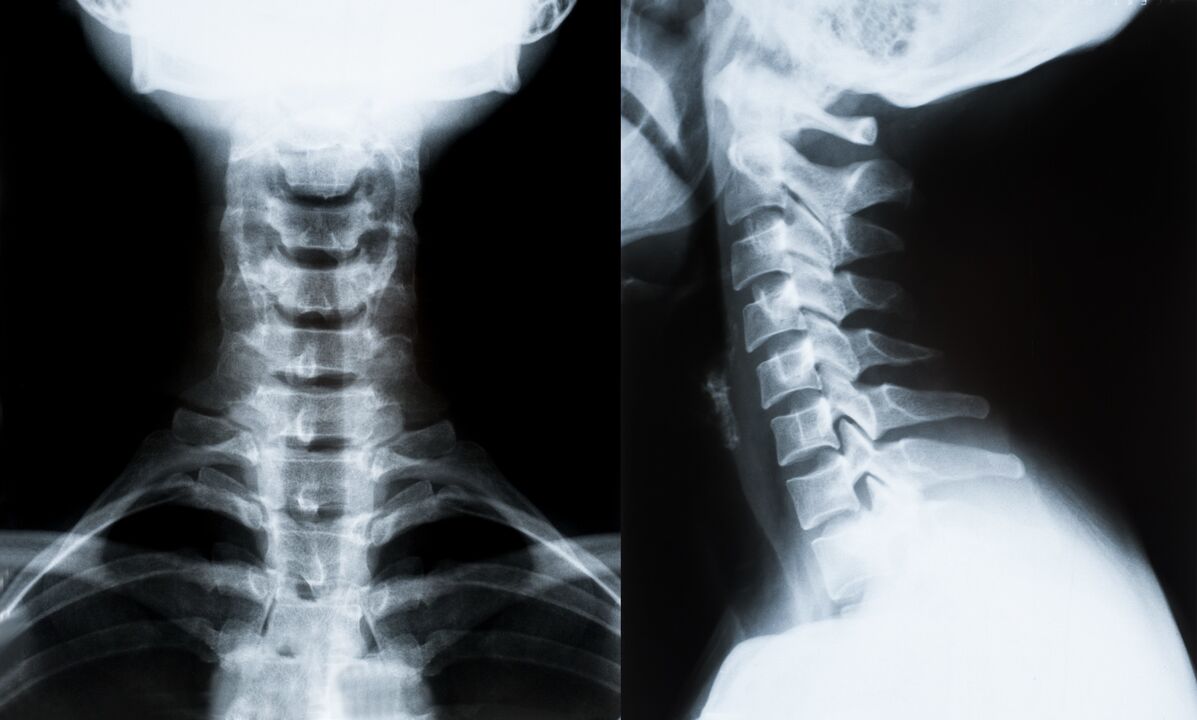

D'Haaptrei Methoden vun Diagnos a weider Determinatioun vun Behandlung fir osteochondrosis vun der cervical Wirbelsail:

- Röntgen. Déi mannst effektiv, awer traditionell diagnostesch Method.

- Magnéitesch Resonanz Imaging ass déi effektiv diagnostesch Method. Mat dëser Aart vun Untersuchung vum Patient sinn all déi néideg Strukture sichtbar.

- Wann Ännerungen musse gemooss ginn, gëtt Computertomographie benotzt. Bestëmmt d'Präsenz vun Hernias an aner Saachen.

- Déi lescht Method ass Ultraschall Duplex Scannen. Dës Fuerschungsmethod bestëmmt d'Geschwindegkeet vum Bluttfluss an den Arterien.